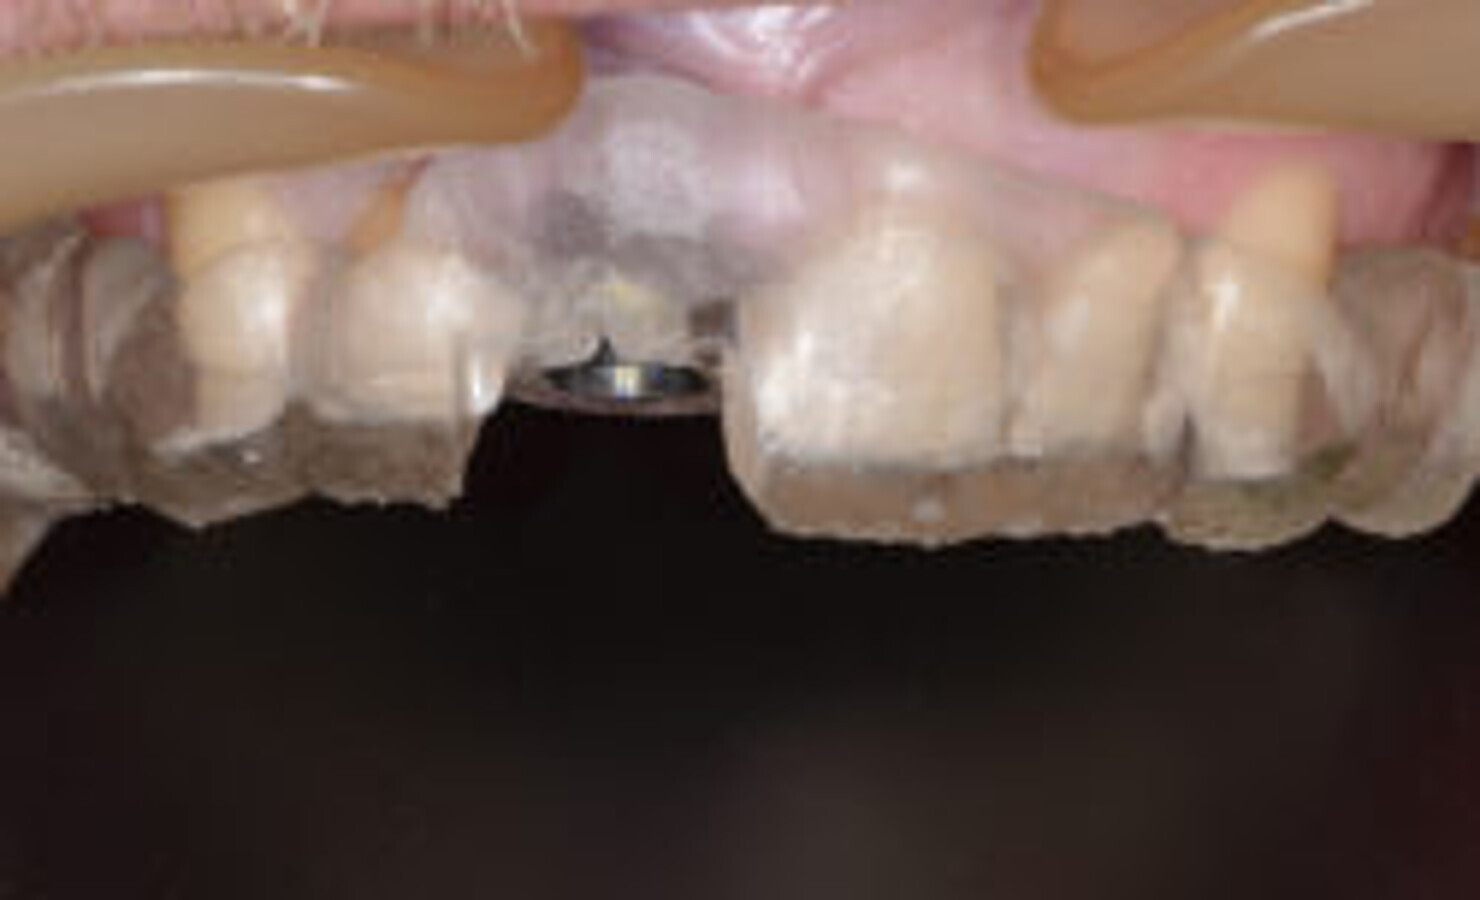

应用 CEREC瓷睿刻 Omnicam scanner 真彩扫描(登士柏西诺德)进行上下颌颊面全角度扫描(图3)。所得图像与DICOM(医学数字成像与通信)文件一同被上传至Simplant software(登士柏西诺德,图4&5)。

图3. 上下颌咬合位唇面重建:绝对需要设计牙冠。